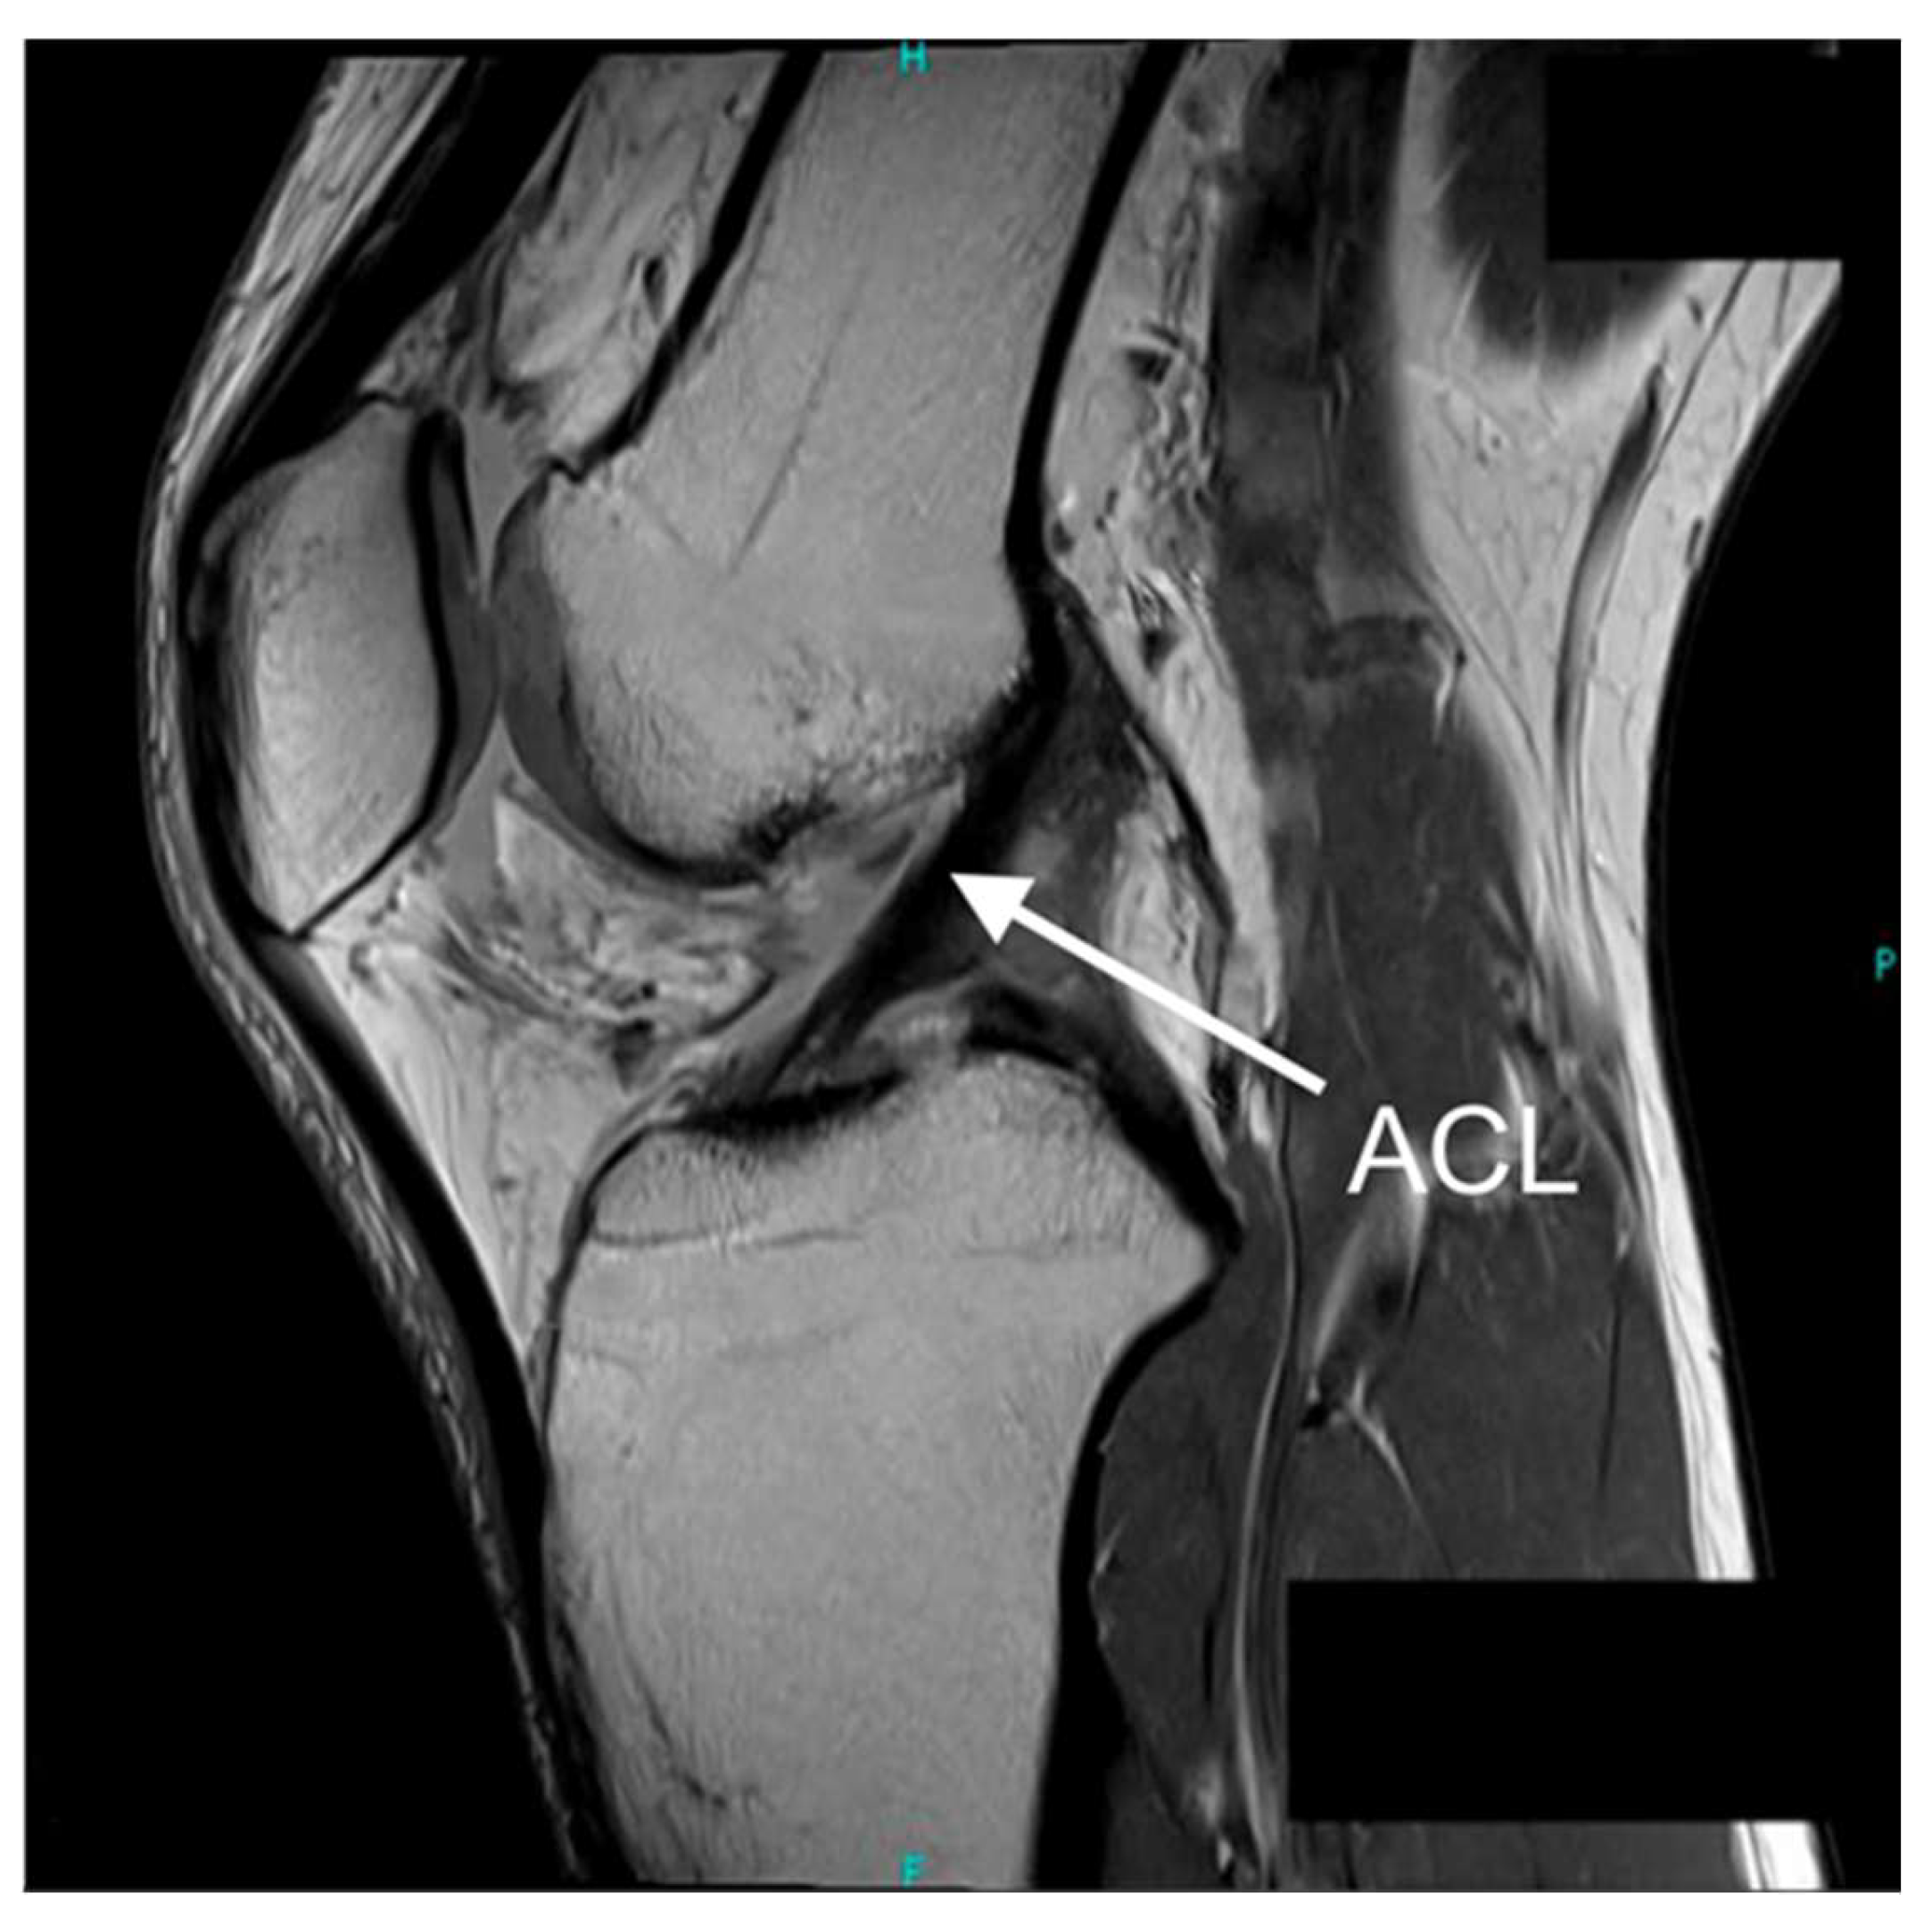

| ACL | Anterior Cruciate Ligament |

| MRI | Magnetic Resonance Imaging |